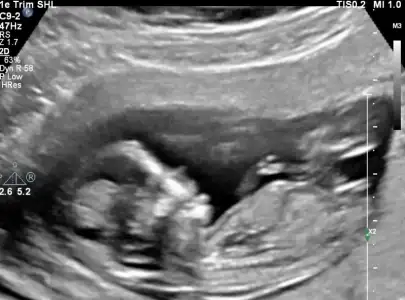

nub teorisi var canim resim at bakalim nasil

Herkese selam az önce doktordan geldim kızlar 3 hafta önce yüzde 80 erkek dedi bugün de yüzde 80 kız dedi sinir oldum bugün doktora vitamin yazmayacakmisiniz diyorum kadın yooo gerek yok gibi diyor ama hic bir değerime bakmadan bu nasıl bir şey yaa şimdi bebeğim kız mi erkek mi offf offf hayırlısı diyelim en iyisio_O